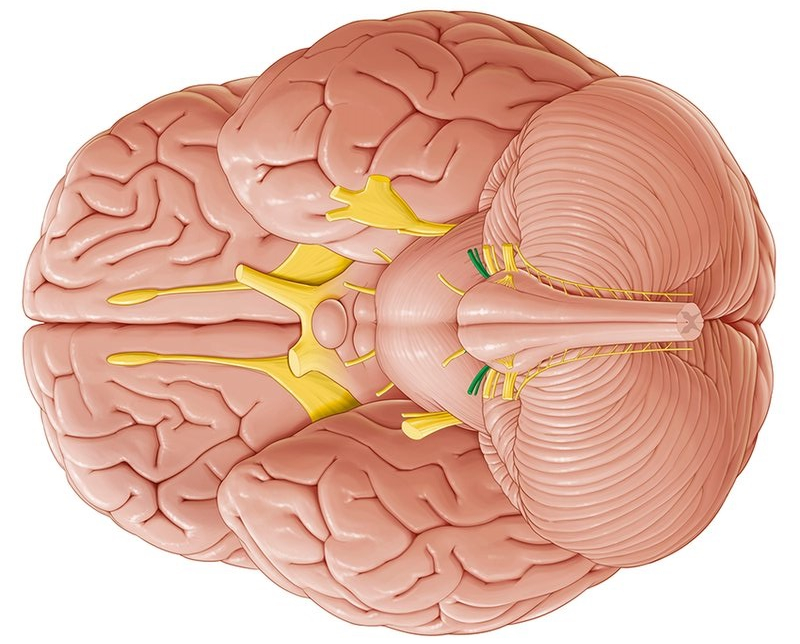

No, we’re not moving away from the spine, but we are talking about the cranial nerves.

It’s day thirty-four in our spinal cord series. As usual, if you’re new here welcome and you can find each and every post in our series in the handy neuroanatomy category! All the posts are in reverse chronological order and while we don’t technically have a specific order, you should probably start with the medullary pyramids and work your way forward. If you’re here, then you probably are interested in the vestibulospinal tract, something we haven’t covered yet, but fear not, we are going to do that now.